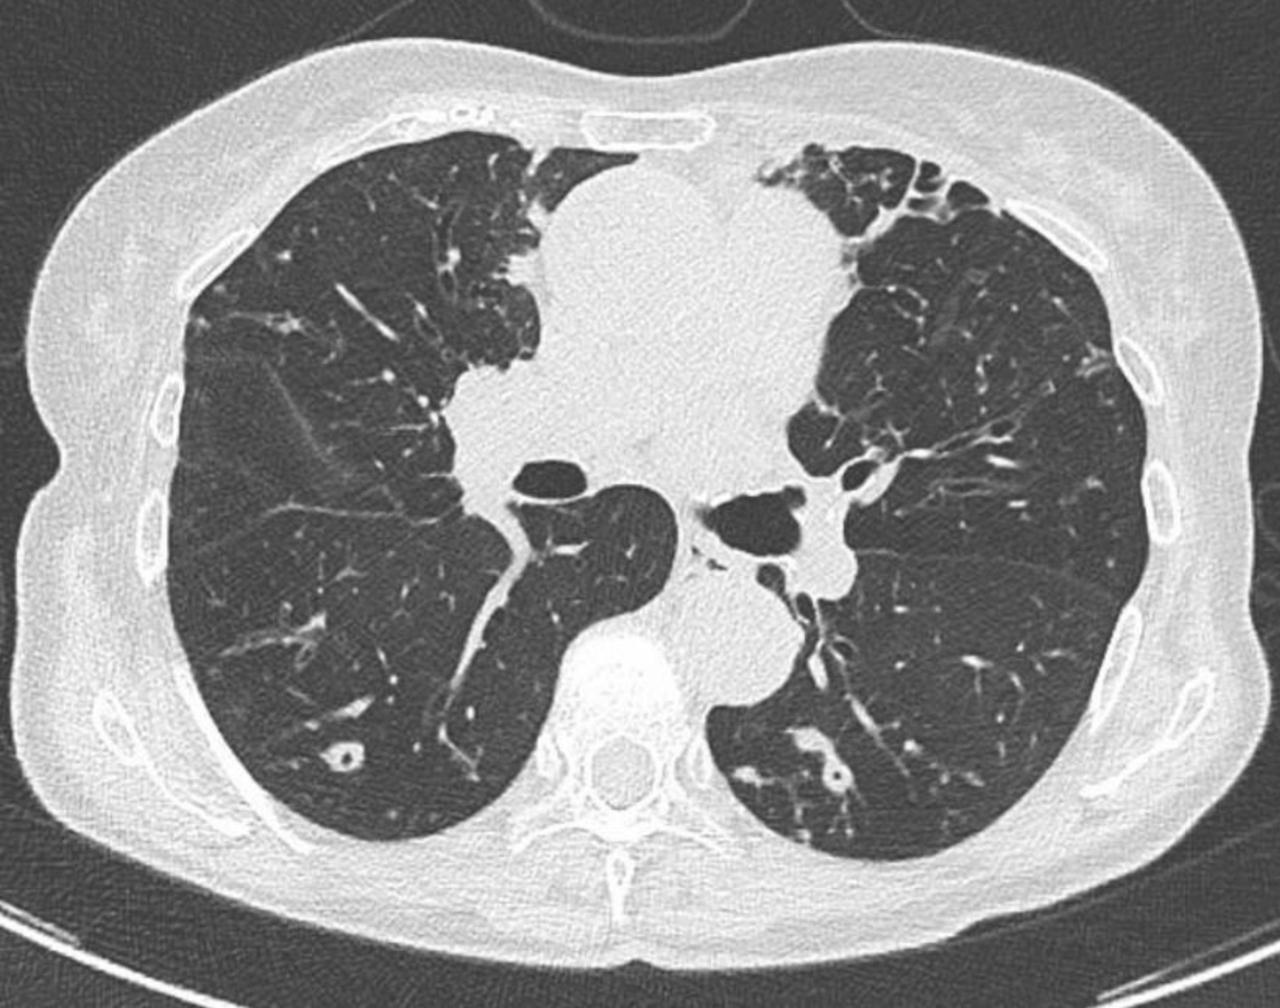

Vous réalisez donc les examens complémentaires suivants : – ETT sans anomalie notable – notamment pas de lésion valvulaire identifiée ; – fond d’œil sans foyer de rétinite ; – charge virale sérique CMV négative. Charge virale sérique EBV à 1,5 log ; – PCR nasopharyngée SARS-CoV-2, influenza et virus respiratoire syncytial (VRS) négative. Vous réalisez une TDM-TAP injectée qui ne retrouve pas d’anomalie notable à l’étage sous-diaphragmatique, notamment pas de foyer profond ni de polyadénopathie. Pas de lésion parenchymateuse hépatique ou splénique. À l’étage thoracique, vous identifiez en revanche ces lésions : Figure (Julien Derdevet, La Revue du Praticien)

La présence de nodules pulmonaires chez un sujet immunodéprimé – en dehors des causes tumorales – peut faire évoquer plusieurs étiologies infectieuses – bactériennes (Cocci à Gram positif ou germes intracellulaires, mycobactéries typiques (M. tuberculosis) ou atypiques, nocardiose...), fongiques (aspergillose, mucormycose, cryptococcose, histoplasmose, coccidioïdomycose...) voire virales. L’examen diagnostique le plus rentable reste donc dans cette situation le LBA. Plusieurs examens non invasifs peuvent toutefois être au préalable réalisés : l’antigénémie sérique galactomannane permet de diagnostiquer une infection à Aspergillus spp. (seul ou en faisant le rapport LBA/sérum), la PCR mucorale sérique a une très bonne valeur diagnostique pour les mucormycoses... Idem pour l’antigène cryptocoque sérique. Le bêta-D-glucane – marqueur antigénique pour presque toutes les infections fongiques en dehors de la cryptococcose et des mucormycoses – serait en revanche ici peu utile, puisque probablement positif dans le contexte de candidémie récente. Il a par ailleurs une cinétique de décroissance lente, ce qui en fait un mauvais marqueur pour le suivi thérapeutique. Enfin, il faut noter que les réactifs sont obtenus à partir d’extraits (sang) de limules – une espèce en déclin de par sa surexploitation. Pour finir, si une réactivation d’une tuberculose latente vers une tuberculose maladie reste possible – surtout chez un sujet né avant les années 1970 – les tests IGRA ou intradermoréaction (IDR) restent de peu d’utilité pour différencier ces deux cadres nosologiques.

Vous réalisez donc un lavage broncho-alvéolaire. Les prélèvements bactériologiques, mycobactériologiques et virologiques reviennent négatifs ; de même que l’anatomopathologie, qui retrouve des cellules inflammatoires aspécifiques. La culture fongique revient positive à Aspergillus fumigatus, avec un antigène galactomannane dans le LBA positif à 1,2. Les PCR mucorales dans le LBA sont négatives. L’antigène galactomannane plasmatique est également positif à 0,9 ; avec des PCR mucorales et un antigène cryptocoque négatives dans le plasma.